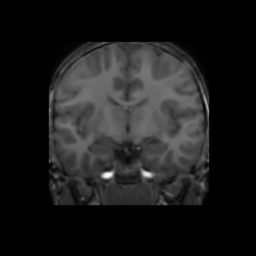

Accuracy is reported as Dice overlaps between a tool's segmentation and the Internet Brain Segmentation Repository (IBSR) manual segmentation for each of the 18 IBSR subjects. The inter-tool comparison (on the left below) shows the median Dice coefficient for each tissue class. The overlaps for FSL (from which the median values are drawn) are shown in the plot on the right.

Overlap coefficients for each tissue class are shown here for each IBSR subject. Select a subject below to see the FSL results compared to other tools.